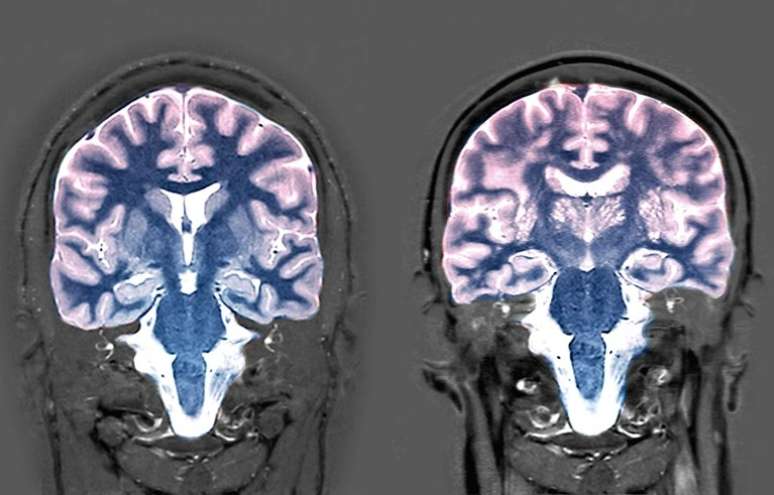

Ressonância magnetica do cérebro de um homem de 25 anos (esquerda) e de um homem de 74 anos (direita).

Foto: Zephyr/Science Photo Library